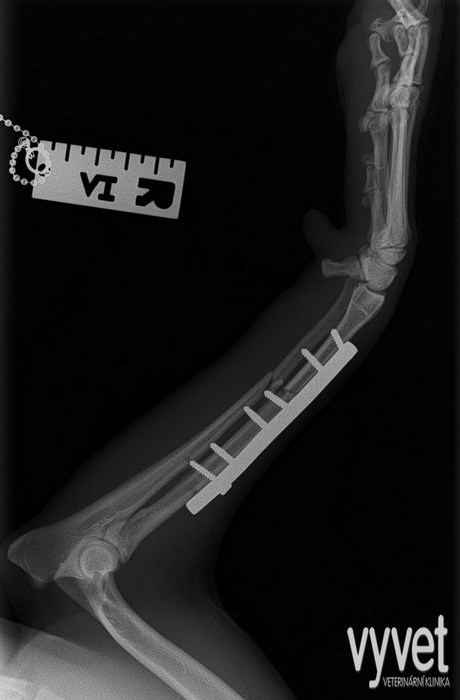

Nejčastějším problémem dlouhých kostí jsou zlomeniny (fraktury)

Rozdělujeme je do několika skupin podle charakteru, množství fragmentů, průběhu linie lomu, dislokace, stability atd.

Je mnoho popsaných metod fixací fraktur. Neinvazivní metodou je přikládání fixačních obvazů a kastů. Tento typ fixace však není ideální, protože nejsme schopni u zvířat zabezpečit dostatečně dlouhou dobu klidu pro srůst kosti. Ideální metodou je invazivnější přístup a to chirurgická repozice s následnou fixací osteosyntetickým materiálem.

Na našem pracovišti používáme zejména ploténky a hřeby.